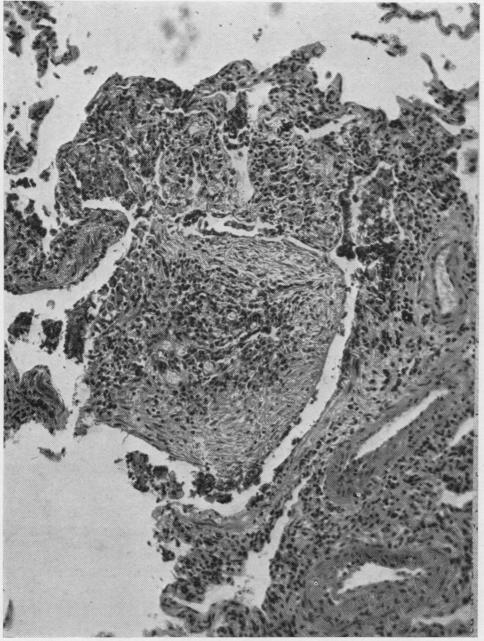

Rheumatoid arthritis with lung lesions.

Thorax. 1956 Sep;11(3):234-40. doi: 10.1136/thx.11.3.234.